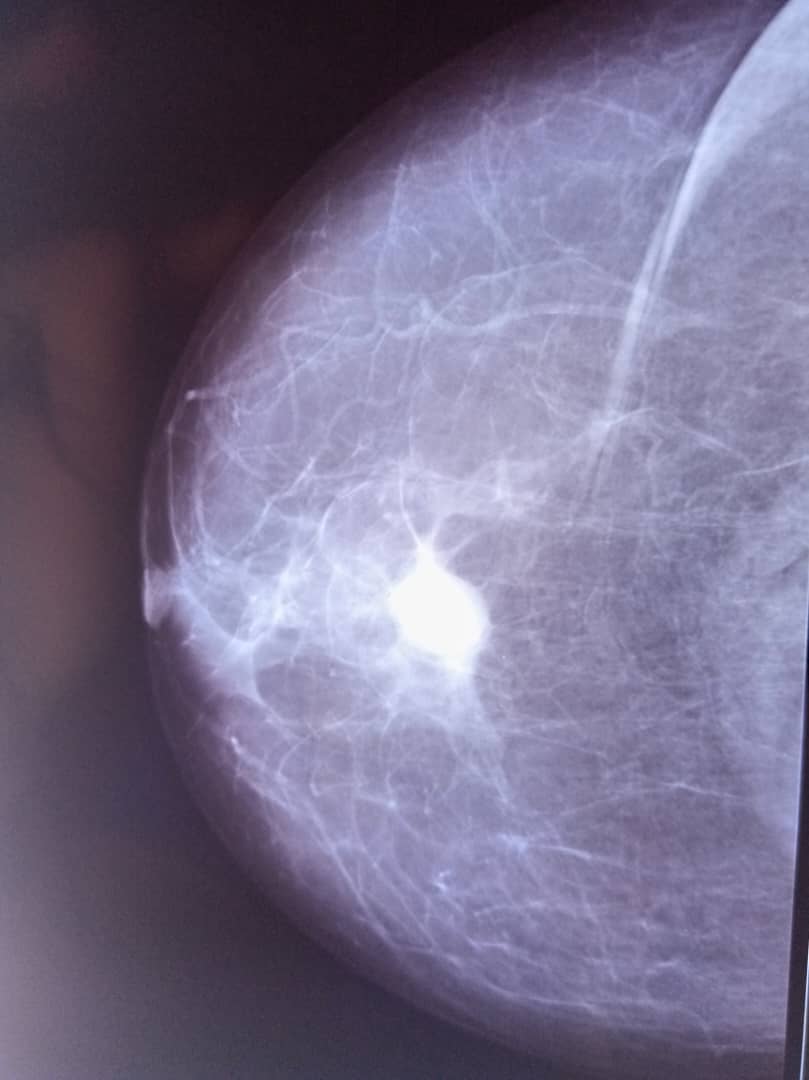

- Mammography

Mammography utilizes low dose x-rays to generate images of the breasts in search for abnormalities especially cancer at its early stage. Although mostly done for women, to screen for and diagnose breast cancer, it is also done occasionally for men with suspicious breast swellings to exclude possible breast cancer.